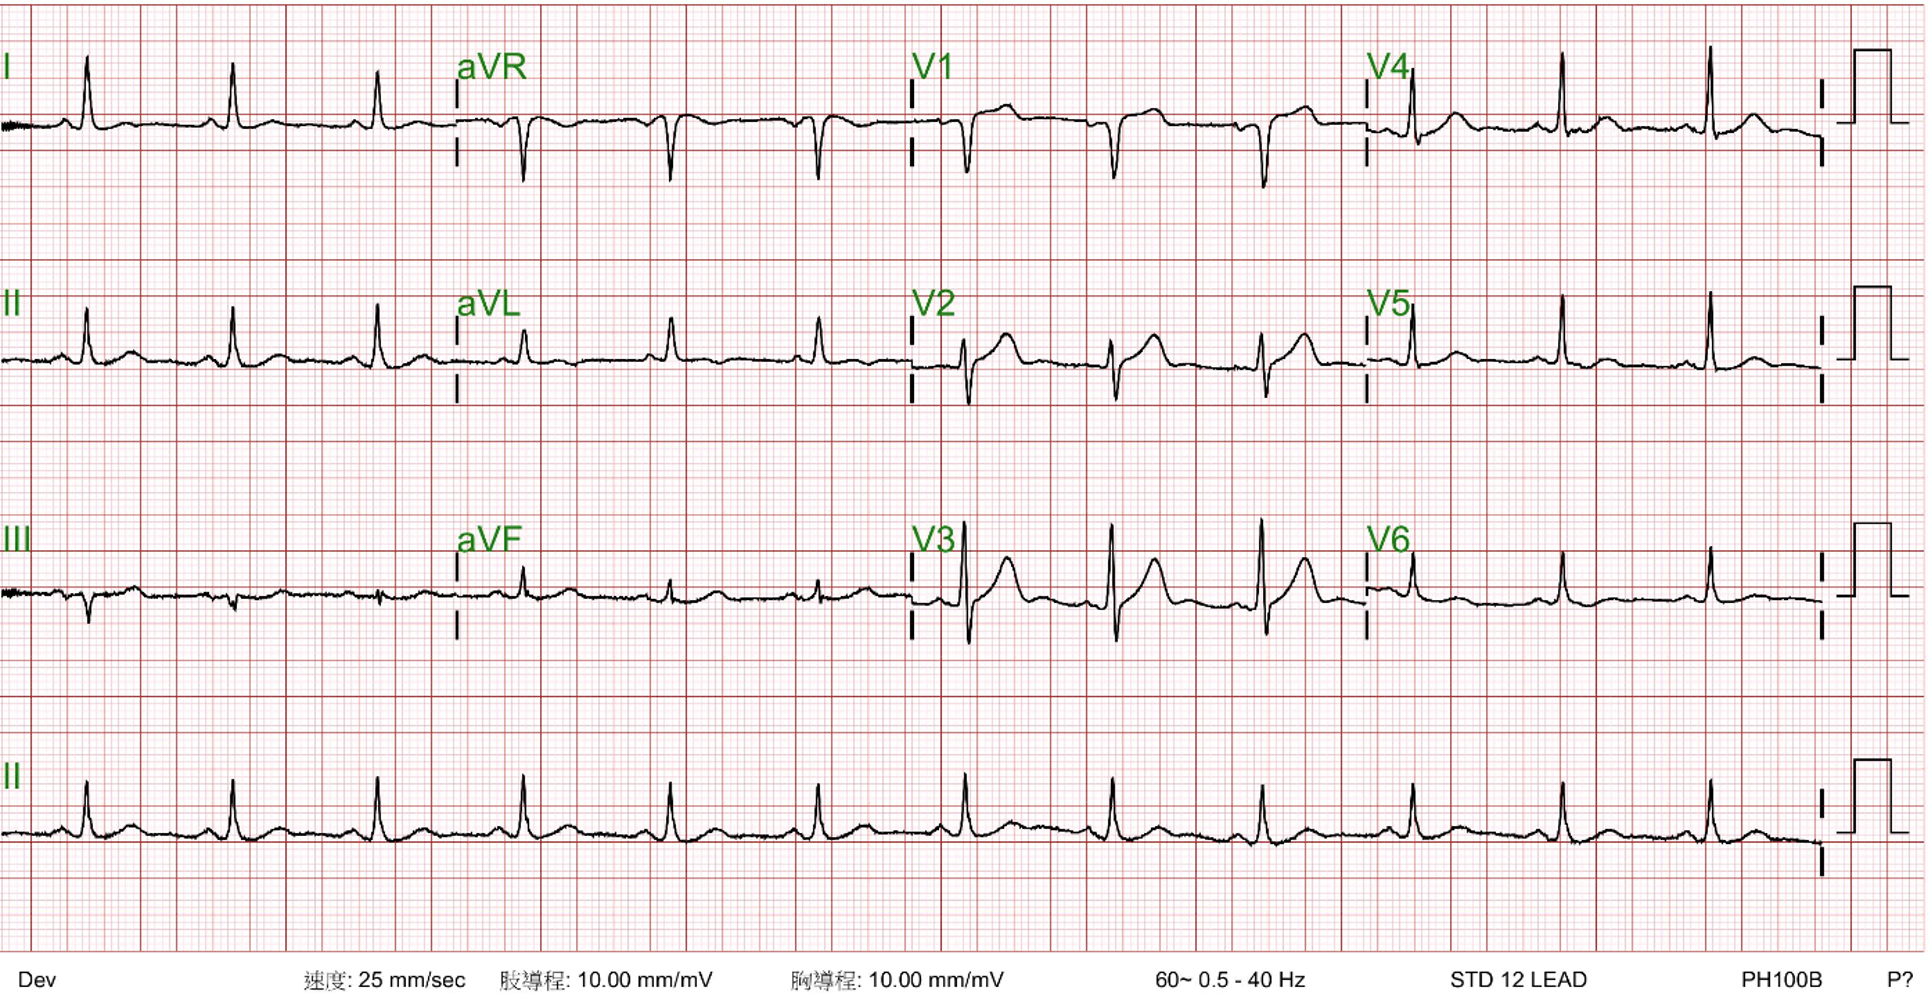

71 year old man with history of HTN, type 2DM and hyperlipidemia

LDL 85 mg/dL; HbA1c 7.6%; Cre 1.1 mg/dL

Diagnosticcoronary angiography revealed: Chronic total occlusion (CTO) in the rightcoronary artery (RCA) with heavy calcification; Diffuse lesion in the leftanterior descending (LAD) artery; Proximal lesion in the left circumflex (LCx)artery; LAD providing collateral flow to the RCA.